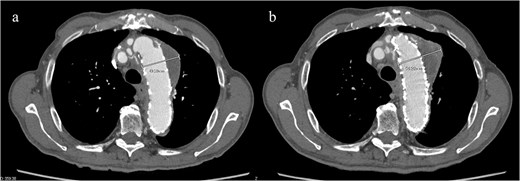

Given the ongoing hemoptysis, presumed aneurysmal expansion due to an occult endoleak, and the absence of any other obvious causes of hemoptysis, we determined that intervention for the aneurysm was necessary. TEVAR was performed using a right femoral artery approach. Initial angiography did not reveal contrast leakage into the sac (Fig. 3a). A 34 × 34 × 200 mm Gore Conformable TAG stent graft (W.L. Gore & Associates, Flagstaff, AZ, USA) was deployed to cover the distal edge of the FET. The second stent graft, a 34 × 34 × 150 mm Gore Conformable TAG stent graft, was deployed overlapping the first graft immediately after the left subclavian artery branch to cover the entire length of the FET (Fig. 3b). Considering the proximal migration, a type Ib endoleak was deemed the most likely cause. However, the possibility of a type III endoleak from the graft was also considered, so the stent graft was deployed to cover the entire area. The patient’s hemoptysis resolved completely postoperatively. A follow-up CT 2 years later showed a reduction in the aneurysm size from 56 to 44 mm (Fig. 4).

(a) Contrast-enhanced CT performed soon after TEVAR showing an aneurysm diameter of 56 mm. (b) Two years later, contrast-enhanced CT showing a reduction in the aneurysm diameter to 44 mm.